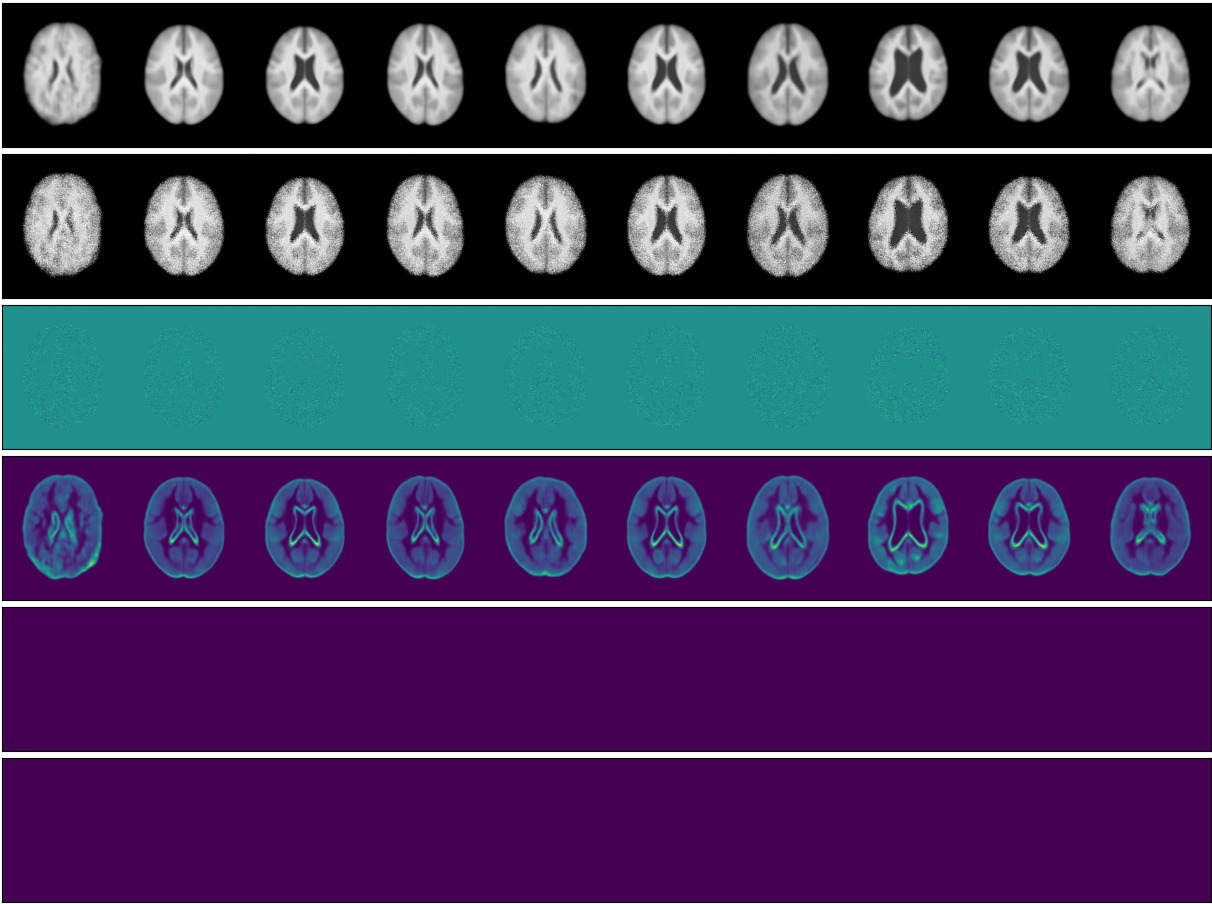

We start by comparing a -VAE, with a pixel-wise independent normal observational distribution, to the proposed SOS-VAE method, with a low-rank multivariate normal observational distribution. We choose a -VAE (Higgins et al., 2017) baseline rather than a standard VAE so that it can be trained using the same Lagrangian method with being a Lagrangian multiplier. This allows for fairer testing since the comparison is between models that differ only by our contributions. This is the only modification to the baseline over a standard VAE. We perform the comparison in two datasets: the CELEBA dataset (Liu et al., 2015) and the UK Biobank (UKBB) Brain Imaging dataset (Miller et al., 2016). For all models, we use a latent space of dimension 128. For the low-rank model, we use a rank of 25. For the CELEBA dataset we use a target KL loss , , of 45 for both models and for our model. For the UKBB dataset we use a target KL loss, , of 15 for both models and for our model. Figures 2(a) & 2(b) and 2(c) & 2(d) show the qualitative results for the comparison.

In Figures 2(a) and 2(c), we see that the samples of the -VAE exhibit uncorrelated pixel noise around the mean, resulting from the pixel-wise independent joint observational distribution. In contrast, in Figures 2(b) and 2(d), we see that the samples produced by our SOS-VAE contain semantically-meaningful variations around the mean and are spatially coherent, as illustrated in the difference (row 3) between the mean (row 1) and the sample (row 2). Looking at the variance of the two methods (row 4), we see a significant difference in the regions where each model is uncertain, highlighting the difference in behaviour between the two predicted distributions. The predicted covariance (rows 5 and 6) for the low-rank model contains a structure that pertains to the image content. These figure rows represent positive and negative covariance to the central pixel indicating global covariance can is modelled. This structure results in spatially coherent samples as opposed to the noisy samples of the -VAE, which are a consequence of the diagonal covariance. Interestingly, we observe more variation in the means of the -VAE, suggesting that as more variation can be modelled in the observation space, less needs to be modelled in the latent space.